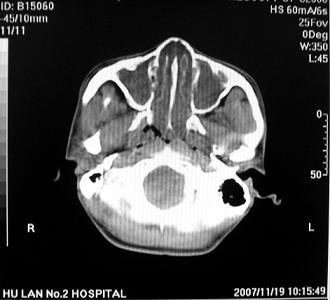

标题: CT10521:男。32岁,副鼻窦ct,请会诊。

男。32岁,鼻塞,流涕一年余。

软组织密度影填满上颌蚪 筛窦及鼻腔,并导致筛骨 上颌窦内侧壁明显骨质破坏。多考虑:内翻性乳头状瘤!

鼻窦炎伴息肉形成可能,上颌窦内侧壁明显骨质破坏并无挤压,膨胀改变,多不考虑内翻性乳头状瘤.

双侧鼻腔内低密度软组织影,骨壁无明显破坏,鼻腔无扩大,双侧上颌窦、筛窦软组织影,窦壁增厚,结合临床考虑鼻息肉合并慢性上颌窦炎。